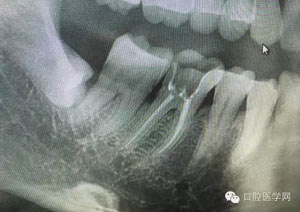

病例1:患者迫切希望保留自己的這一顆牙齒,根尖周陰影比較大,二度松動(dòng).而且旁邊有種植修復(fù)體,和患者溝通好后,治療好后觀察一個(gè)月后冠修復(fù),因?yàn)橛蟹N植的后期修復(fù),所以有了機(jī)會(huì)觀察,術(shù)后三個(gè)月和術(shù)后四個(gè)月,根尖恢復(fù)的還算不錯(cuò),希望能夠繼續(xù)觀察下去.這樣子的病例,做的時(shí)候我們一定要非常的小心,和患者要有充分的溝通以及不同科室的溝通然后決定怎么樣做比較好,假如就是出現(xiàn)了問(wèn)題,到時(shí)候我們也比較好處理些,免得我們自己到時(shí)候不好收?qǐng)觥?/span>